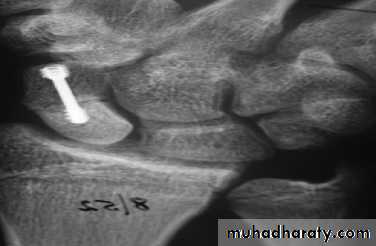

1-Undisplaced fractures need no reduction and are treated in plaster. The cast is applied from the upper forearm to just short of the metacarpo-phalangeal joints of the fingers, but incorporating the proximal phalanx of the thumb. The wrist is held dorsiflexed and the thumb forwards in the ‘glass-holding’ position. It is retained for 8 weeks. After 8 weeks the plaster is removed and the wrist examined clinically and radiologically. If there is no tenderness and the x-ray shows signs of healing, the wrist is left free; a CT scan is the most reliable means of confirming union if in doubt.If the scaphoid is tender, or the fracture still visible on x-ray, the cast is reapplied for a further 4 weeks.

After that either the fracture united with pain free or end with non union and in this case need bone graft and internal fixation by herbert screw.

Scaphoid frcature

2-Displaced fractures can also be treated in plaster, but the outcome is less predictable. It is better to reduce the fracture openly and to fix it with a compression screw.